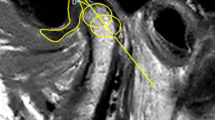

The computational model was validated by using three methods. First, we compared the maximum principal logarithmic strain in the linear elastic range (corresponding to a bar displacement of 1.5 mm), as predicted by the FEA model with the maximum principal true strain measured using DIC (Fig. 2a, c). Second, we compared the force-displacement graphs (Fig. 2b). Lastly, we compared the x and y displacements of the sixth screw (Fig. 2a) relative to the bar displacement (i.e., the z-displacement) between FEA and DIC (Fig. 2d).

a Comparisons between digital image correlation (DIC) and FEA in the strain distributions on the surface of the implant (together with the artificial cartilage), around the condylar neck, and resection border. b The results obtained from the quasi-static compression testing for biomechanical evaluation. c The Pearson similarity between FEA and DIC in three different regions chosen in (a). d Comparisons in the x and y displacements of screw No. 6 with respect to the bar displacement (in the z-direction) between FEA and DIC. e Von Mises stress distributions of different cartilage designs. The legends in (b) apply to (d) as well.

High strains were observed on the implants together with the cartilage-mimicking component around the condylar neck and near the resection border on the superior side of the first and second screws (Fig. 2a). The strain contour plots from DIC and FEA on the ramus area showed similar distributions, with strain values in the three regions (i.e., sigmoid notch, posterior border of the ramus, and mandibular angle) closely matching by factors of 1.07 and 1.3 for the intact mandible and the implant with a hard-soft cartilage-mimicking component, respectively (Fig. 2c). Pearson’s correlation coefficients of r = 0.99 for the intact mandible and r = 0.94 for the implant with the hard-soft cartilage indicated a strong linear correlation between DIC measurements and FEA predictions (Fig. 2c).